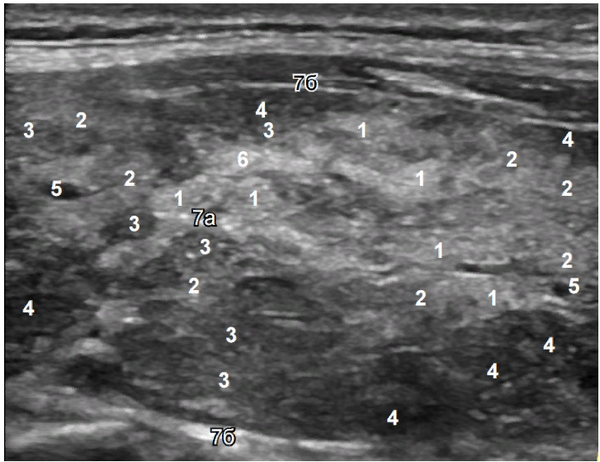

А вот как эти виды эхогенности определяются на реальном ультразвуковом снимке:

Обозначения на снимке:

1 — изоэхогенность (нормальная ткань),

2 — малая гипоэхогенность,

3 — умеренная гипоэхогенность,

4 — значительная гипоэхогенность,

5 — анэхогенность (сосуд),

6 — малая гиперэхогенность,

7 — значительная гиперэхогенность (соединительнотканные структуры).

Буквами обозначены: а — соединительнотканная перегородка, б — капсула железы.

Интерпретация изображения

На представленном снимке можно видеть:

• Участок 1 — дольки с нормальной, здоровой тканью щитовидной железы.

• Участок 2 — дольки с начальными изменениями, такими как отек стромы (основы ткани) и признаки истощения.

• Участки 3 и 4 — дольки с выраженным истощением ткани и инфильтрацией иммунными клетками (лимфоцитами).

• Участок 5 — кровеносный сосуд (анэхогенная структура).

• Участок 6 — зона, которая может соответствовать соединительной ткани или ранним признакам регенерации (восстановления) ткани. Подробнее о процессе регенерации мы поговорим в отдельном уроке.